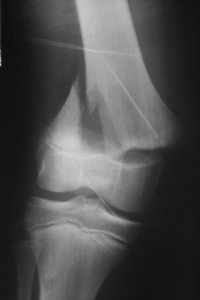

Exemples de décollements épiphysaires Salter 2